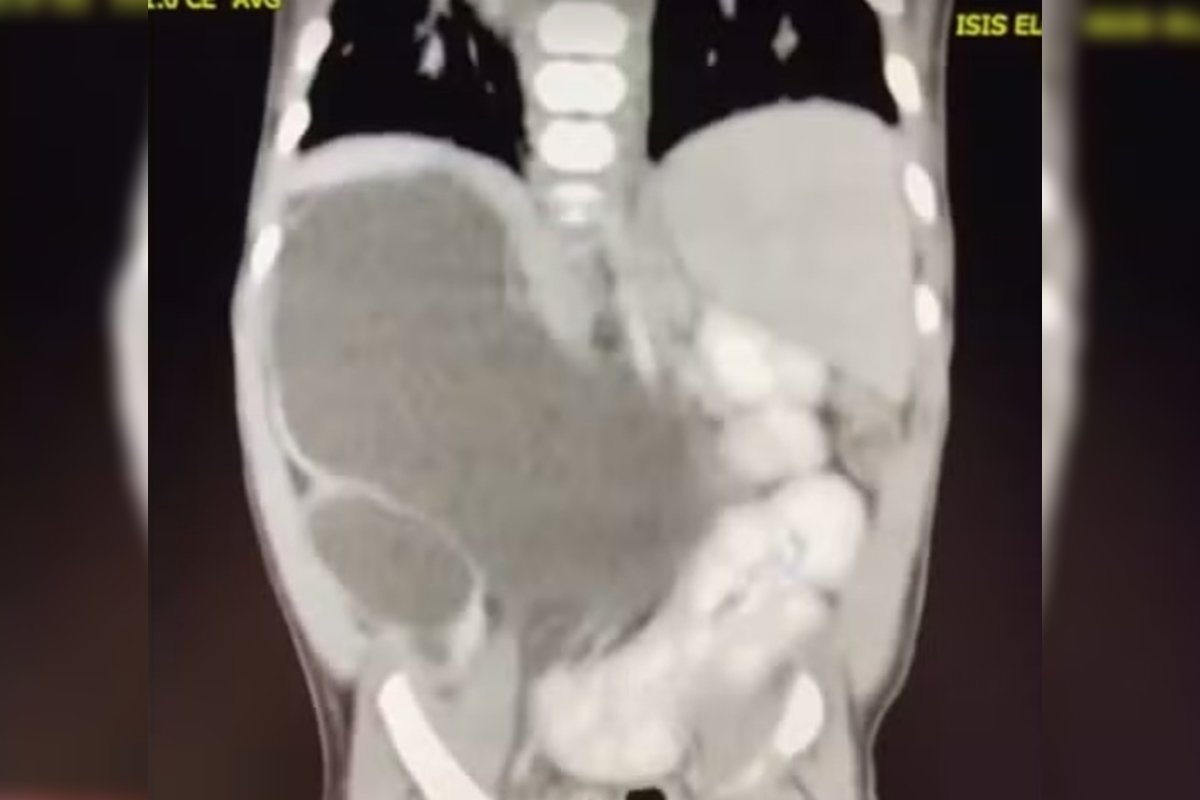

Isis Eloah Ferreira Alves, uma menina de 1 ano e 1 mês, é um dos raríssimos casos na medicina mundial, nascendo com quatro rins, uma condição conhecida como "rins supranumerários". Atualmente, ela faz parte do seleto grupo de cerca de 100 casos documentados na literatura médica global.

Aos 5 meses, durante uma cirurgia, a confirmação veio: Isis Eloah nasceu com quatro rins. Dada a proximidade de Formosa ao Distrito Federal, ela agora recebe tratamento no Hospital da Criança de Brasília (HCB).